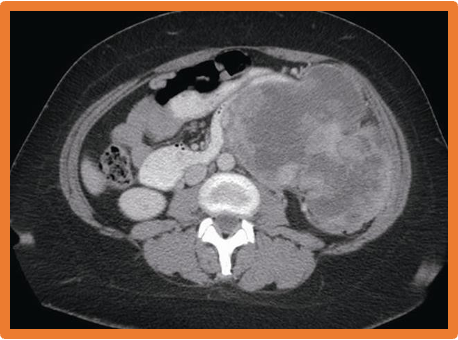

Retroperitoneal Sarcoma-

- Asymptomatic abdominal mass

- (Often- considerable size).

- CT, MRI